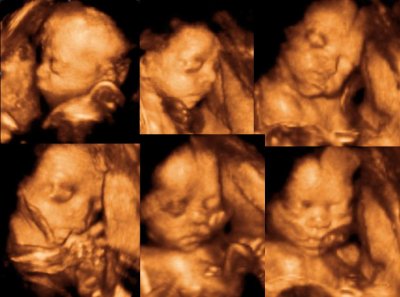

les échographies destinées à fournir aux parents des films en 3D de leur fœtus seraient dangereuses pour les bébés. Les gynécologues et obstétriciens ont donc aujourd’hui tiré la sonnette d’alarme.